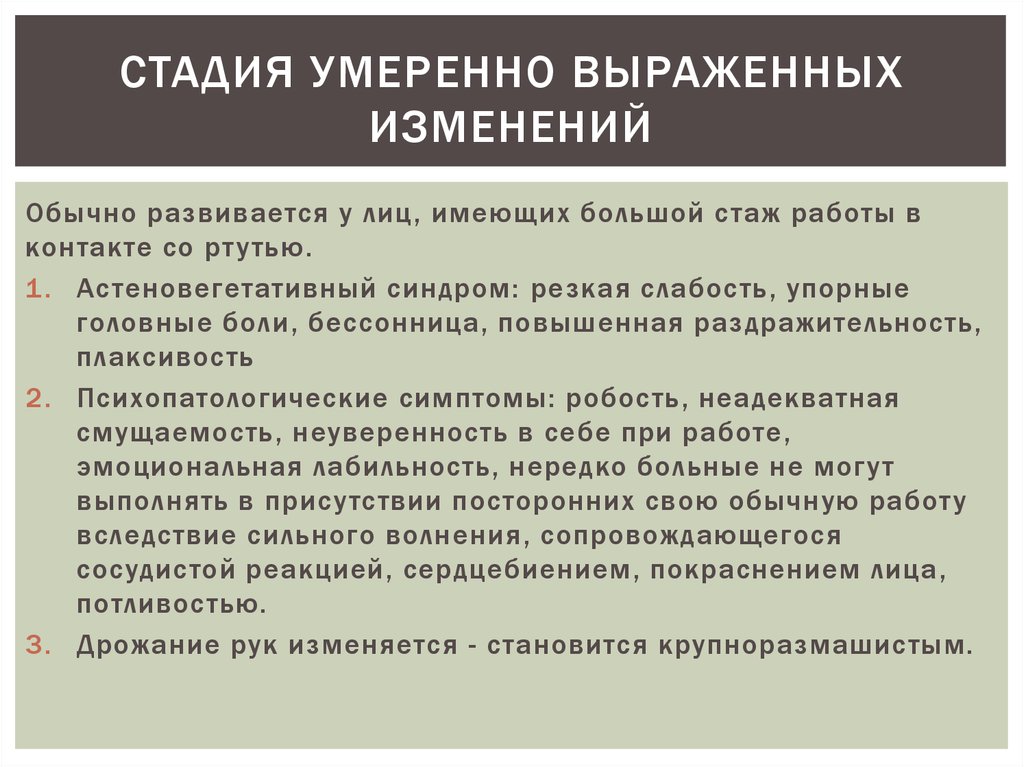

Признаки умеренно выраженной наружная

Признаки умеренно выраженной наружная 113 фото